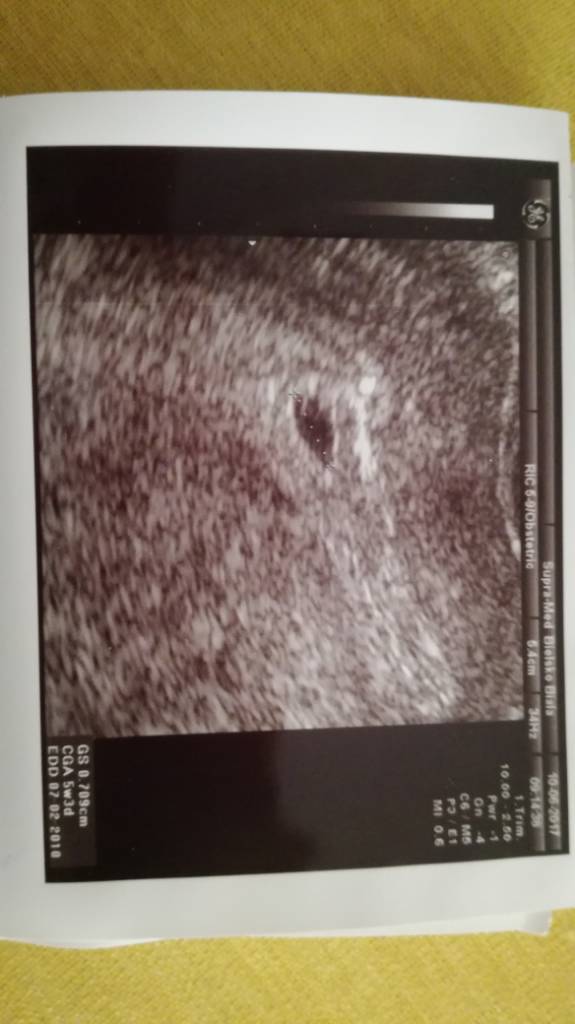

bylam u lekarza, zrobil mi usg i widac bylo pecherzyk 7cm z cialkiem żółtym take powiedzial ze jest ok. Mam luteine na te moje ciągnięcia i kłucie w podbrzuszu. Wedlug usg 5tydz i 3dni

w załączeniu zdjecie

Mamazbb śliczny okruszek,te pierwsze zdjęcia są bardzo wzruszające,z takiej kropeczki urośnie maluszek,cud!